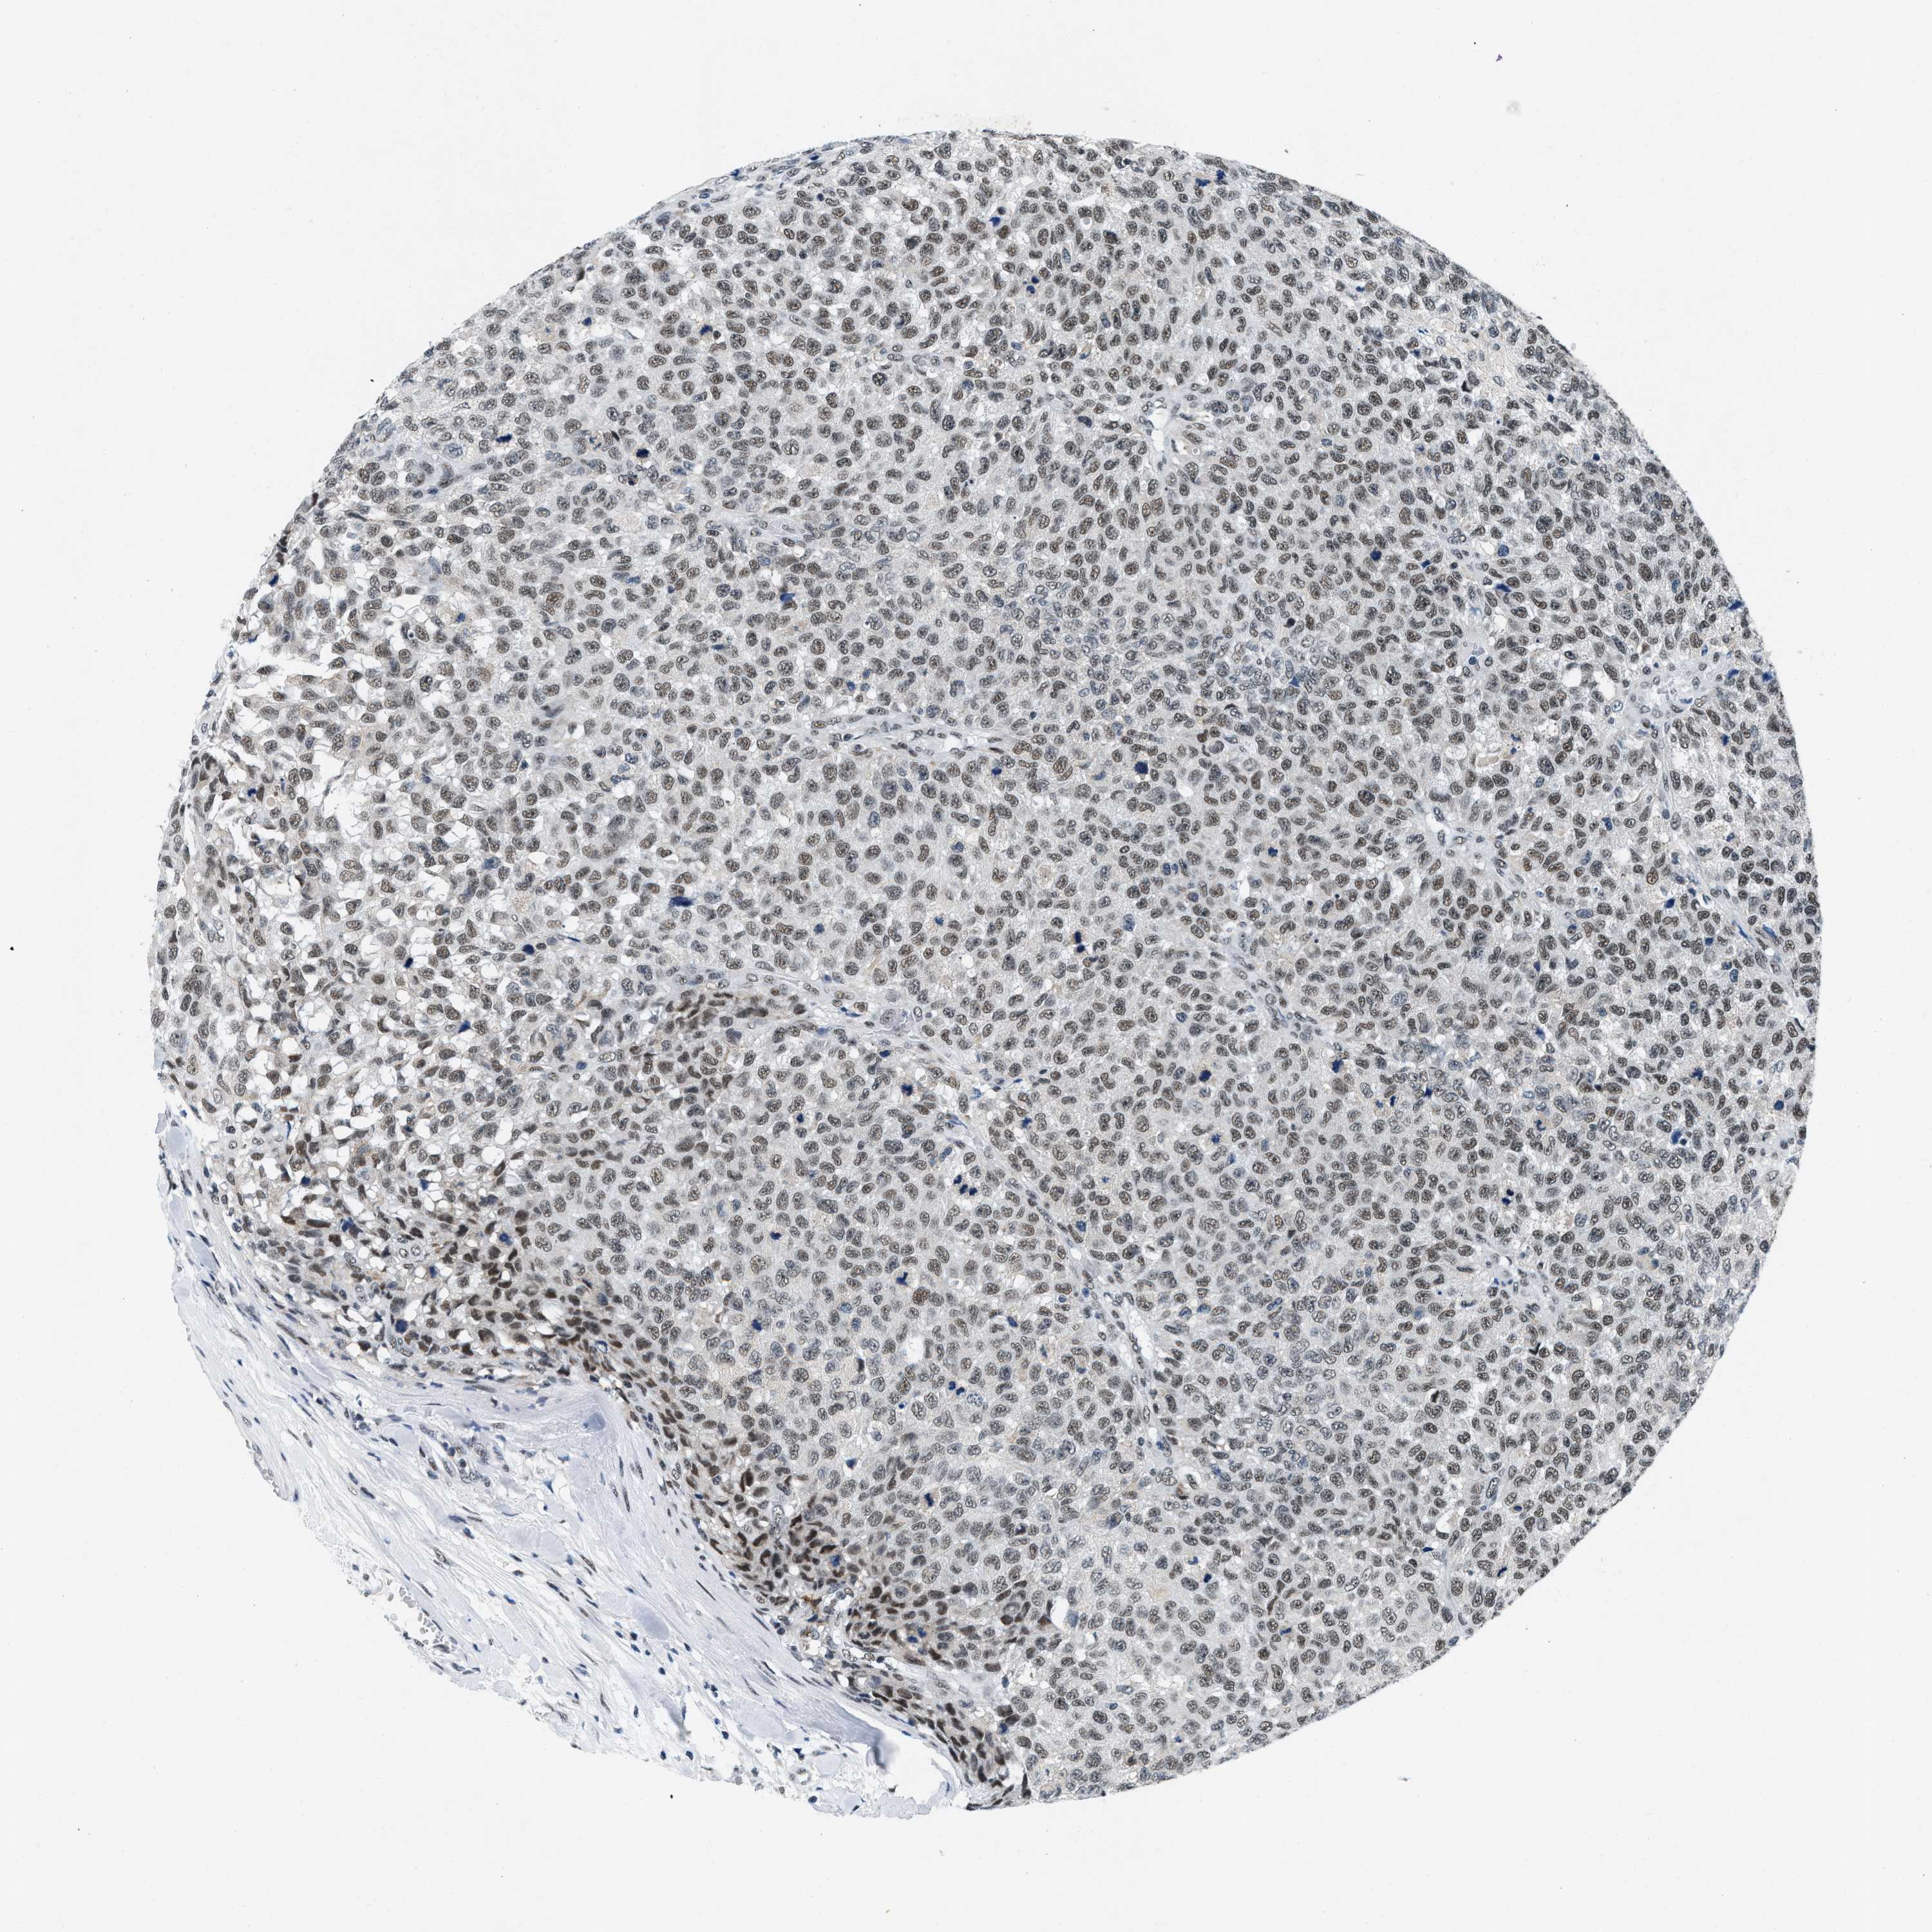

TESTIS CANCER - Protein expressioni

A mouse-over function shows sample information and annotation data. Click on an image to view it in a full screen mode. Samples can be filtered based on level of antibody staining by selecting one or several of the following categories: high, medium, low and not detected. The assay and annotation is described here.

Note that samples used for immunohistochemistry by the Human Protein Atlas do not correspond to samples in the TCGA dataset.

Antibody stainingi

Antibody staining in the annotated cell types in the current human tissue is reported as not detected, low, medium, or high, based on conventional immunohistochemistry profiling in selected tissues. This score is based on the combination of the staining intensity and fraction of stained cells.

Each image is clickable and will lead to virtual microscopy that enables deeper exploration of all samples and also displays staining intensity scores, fraction scores and subcellular localization as well as patient and tissue information for each sample.

Antibody CAB003769

Carcinoma, Embryonal, NOS

Seminoma, NOS